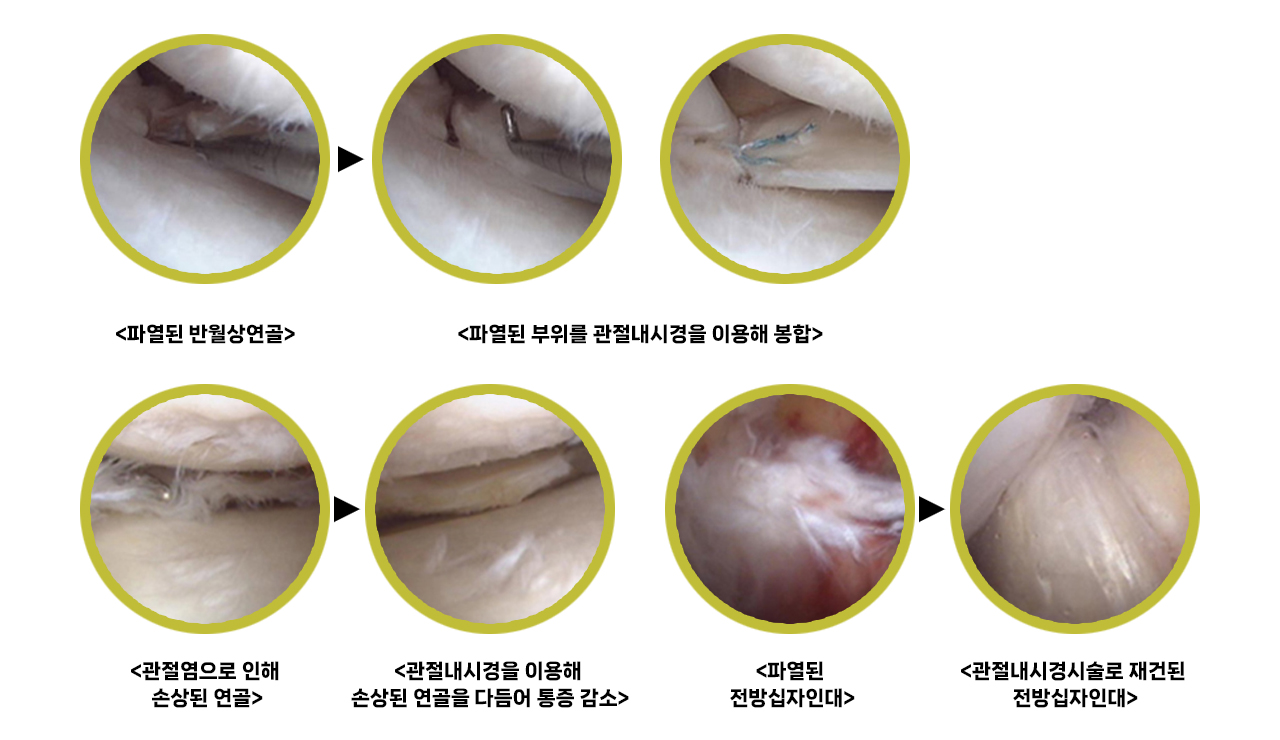

관절내시경 치료 사례

- 파열된 반월상연골판의 부위, 상태에 따라 관절 내시경을 이용한 수술적 봉합술 또는 절제술을 시행

- 전방 십자인대 파열은 단순봉합이 불가능하기에 무릎의 안정성을 유지하기 위해선 재건술 진행

- 수술적 치료 방법에는 관절 내시경, 절골술 및 인공관절치환술등을 환자 상태에 따라 다르게 적용